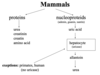

Give the excretory metabolism of mammals